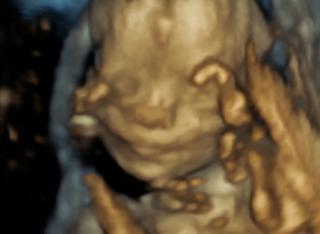

@zuzanazuzana jej ty sa mas,ze uvidis mimi na 3D.... ja ho uvidim az v 30tt myslim,ze vtedy sa az robi ultrazvuk,ci? nestresuj kvoli synovi 😉 ty sa mas praha,waw a ako idete?